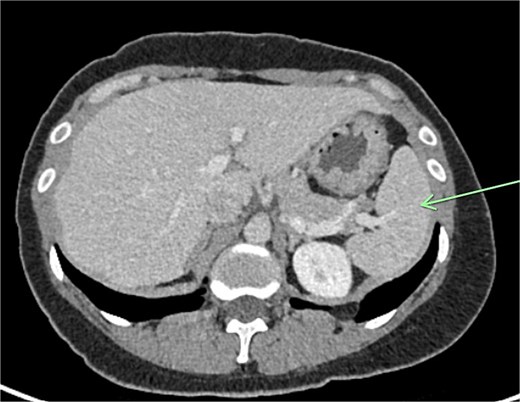

Transvaginal ultrasound demonstrated a large solid vascular mass in the left adnexa measuring 50 × 52 × 54 mm separate to the left ovary. Sonographic appearances of the uterus, endometrium, ovaries, kidneys, and bladder were reported as normal. Computed tomography (CT) demonstrated a solid rounded lesion with moderate enhancement measuring up to 55 mm. This lesion was reported as most likely to represent a broad ligament or pedunculated fibroid.

The aforementioned CT was reassessed intraoperatively together with this new information. The vascular pedicle was traced from the lesion towards the splenic vessels at the tail of the pancreas. A normal spleen was identified in the left upper quadrant (Figs 3–5). The overall impression was that this lesion represented accessory splenic tissue. The general surgery team called the patient’s next of kin, who gave consent to proceed with an excision of this wandering accessory spleen.